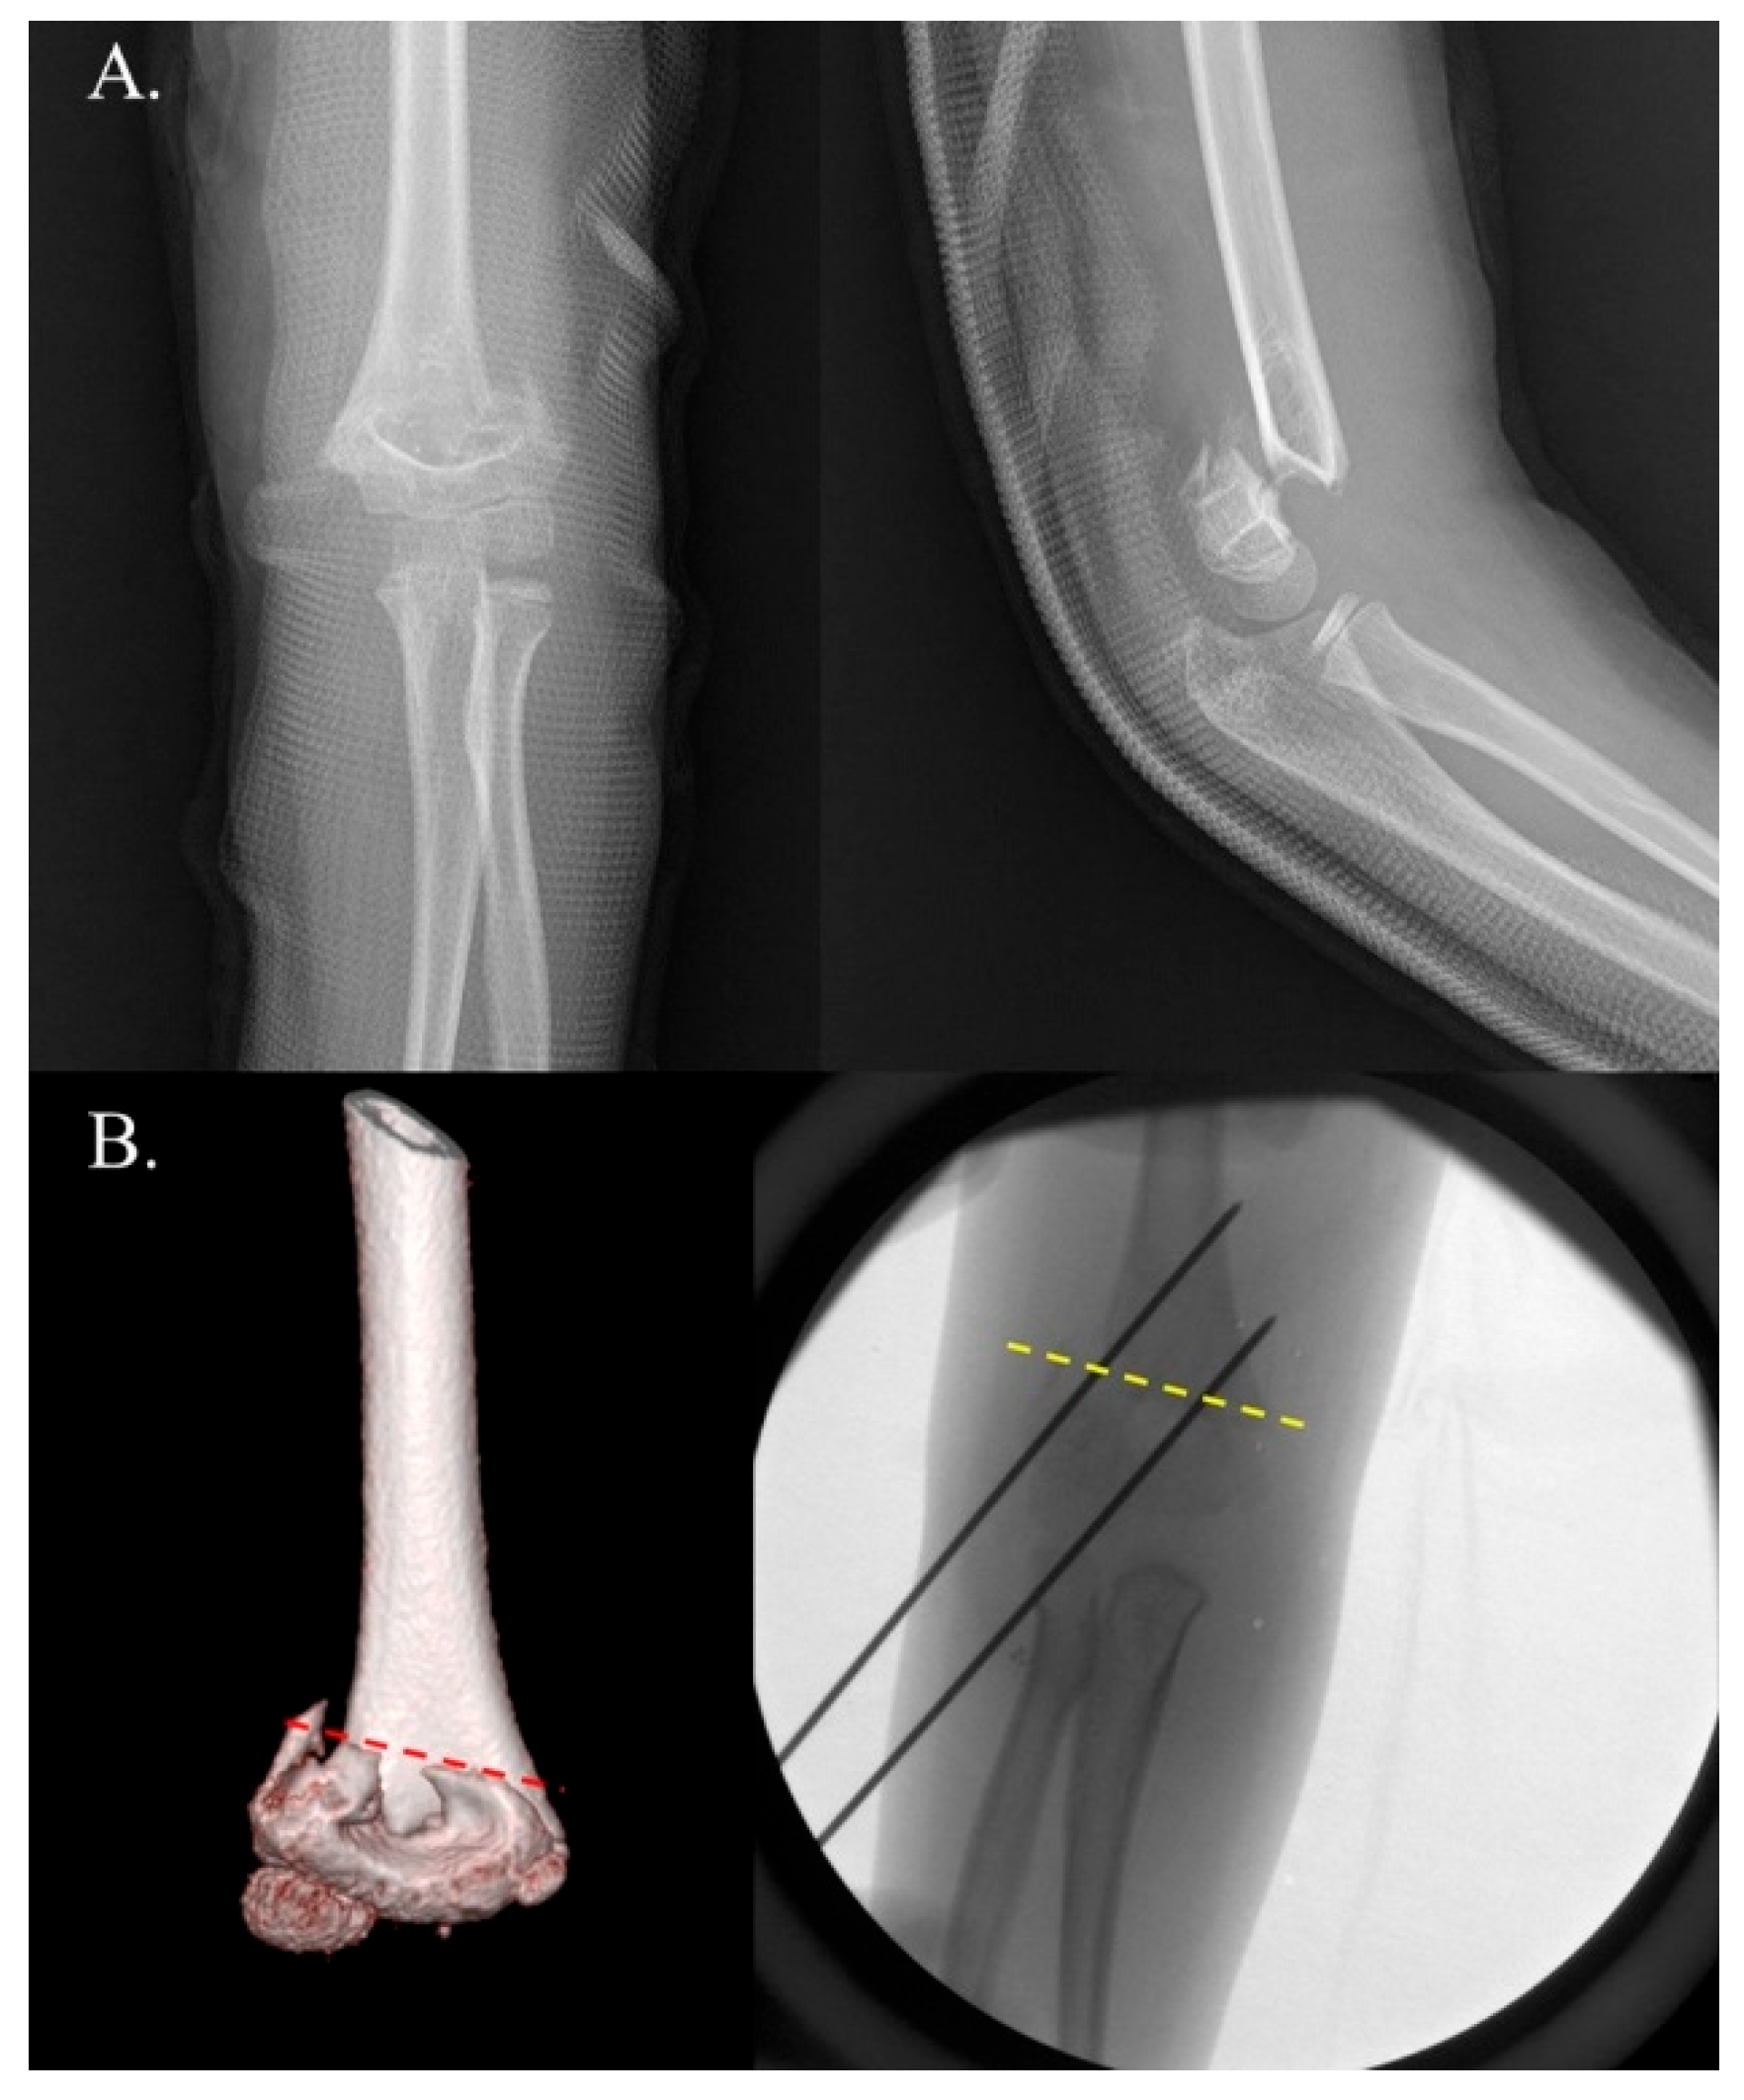

Figure 1. Example of positive internal rotational stress test (IRST) results in a 5-year-old boy with a Gartland type III supracondylar fracture. Panel (A) shows the preoperative radiographs. Panel (B) depicts C-arm images demonstrating a positive IRST. Good bone contact and well-maintained reduction are observed in both the anteroposterior (AP) and external lateral views. However, note (yellow arrow) the loss of reduction due to fragment rotation in the internal stress lateral view.